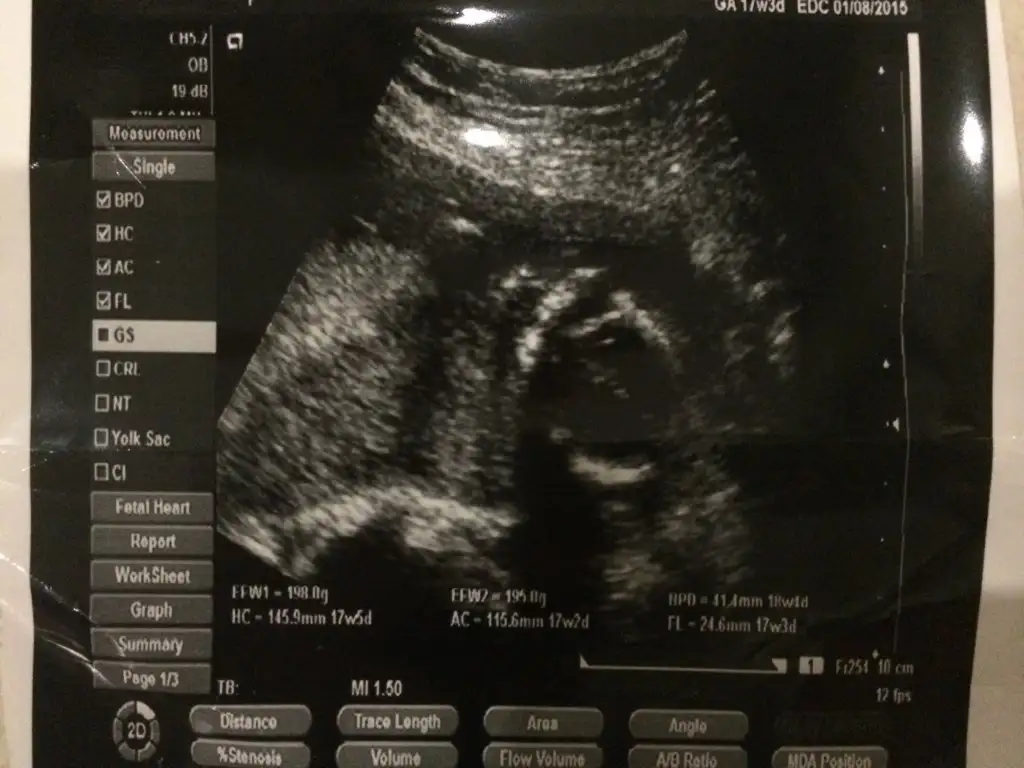

17 haftalıkta var ama onda hiçbişey belli değil bebek bile görmedim ben

Ömrüm bebeğin arkası dönük o yüzden nubu görünmüyor. Birde 11,12,13 haftalık fotosu olması lazım Nub teorisi için

Catladim in kız denilen bebeği oglanmis megersem cocugumuz ağır abi olacak zannimca göstermek istemiyordu